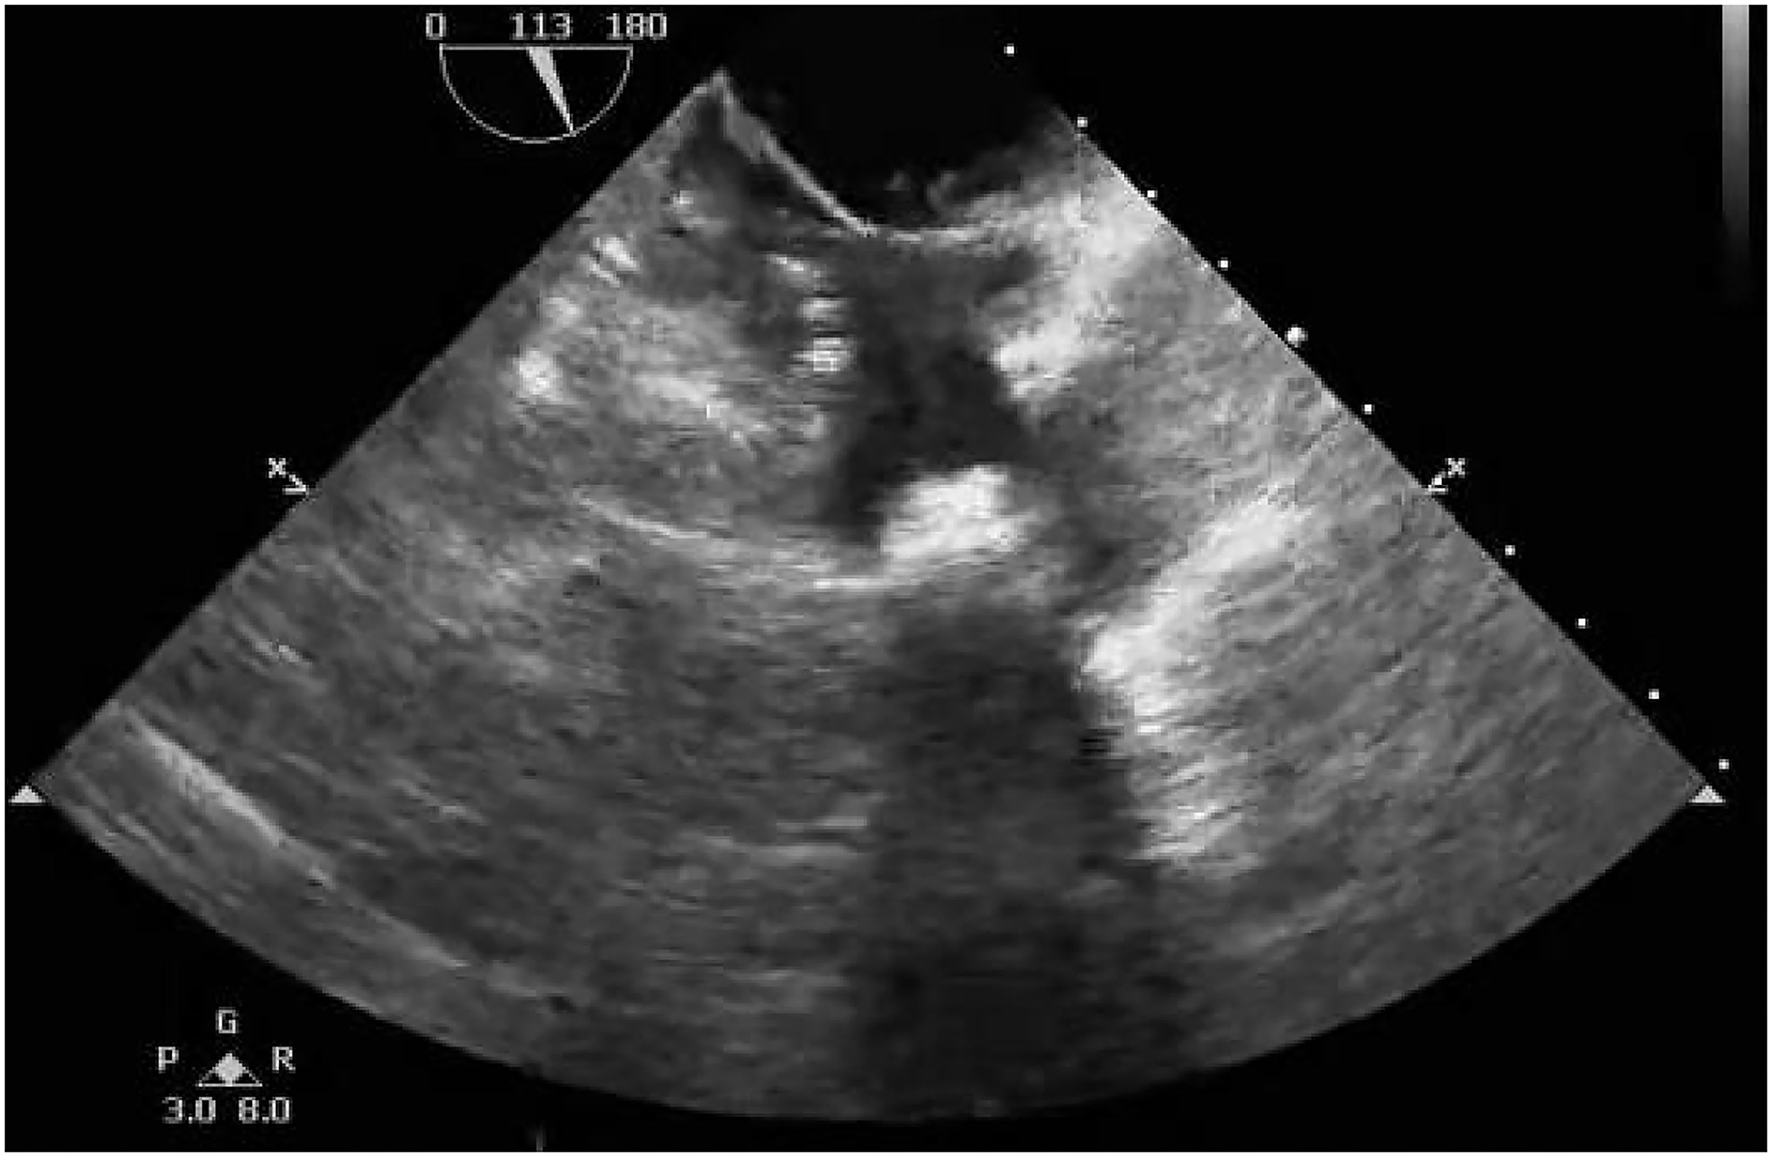

A 40-year-old female with sudden syncope was referred to our department. She has an 18-year history of percutaneous ASD (30 mm in diameter) closure with a 40-mm mushroom umbrella occluder (Huayi Shengjie Co., Ltd., Beijing, China). The surgical result was satisfactory, and no residual shunt was seen. Regular re-examination 3 years after the operation showed no abnormality. Two cesarean sections after 4 and 7 years of percutaneous ASD closure and a hysteromyoma surgery after 13 years of percutaneous ASD closure had been done. Transthoracic echocardiography and electrocardiogram during these three hospitalizations showed no abnormality. The patient in our case has not been followed up and had not undergone transthoracic echocardiography for the last 5 years. In the past 3 months, the patient had two episodes of sudden syncope, one was induced by exercise, and another had no obvious incentive, accompanied by sweating and pale complexion, which was relieved spontaneously in about 5 min. She denied chest pain, chest tightness, shortness of breathing, and palpitations. On physical examination, a soft blowing murmur was heard in the second and third costal margin of the left margin of the sternum. There were no other notable clinical findings during a physical examination and no medical, family, or psychosocial history including genetic information about cardiovascular disease. X-rays (Figures 1A,B) showed that most parts of the closure were deformed, especially the left atrial side (Figure 1B, arrow) and that the nitinol frame of the occluder was not displaced and there was no evidence of a frame fracture. The electrocardiogram demonstrated sinus rhythm and an incomplete right bundle branch block. Transthoracic echocardiography revealed a recurrent significant multi-bundle left-to-right shunt through the device and small adhesions were visible on the occluder (Figure 1C). Moreover, the enlarged right heart chambers and mild mitral valve regurgitation were detected. The patient was eventually diagnosed with a late-onset residual shunt of transcatheter device occlusion of ASD (occluder recanalization).

Figure 1. Chest radiography (A,B) and transthoracic echocardiography (C) preoperatively indicated that most parts of the closure were deformed, especially the left atrial side [(B), arrow]; a significant multi-bundle left-to-right shunt through the device and a small adhesion on the occluder was detected (C).